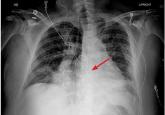

ArticleDancing sternal wires: A radiologic sign of sternal dehiscenceAuthor:Mohamed M. Gad, MDPublish date: February 1, 2019Loose fragments of bone and wire pose a danger of puncturing the heart, making sternal dehiscence a surgical emergency.Read More